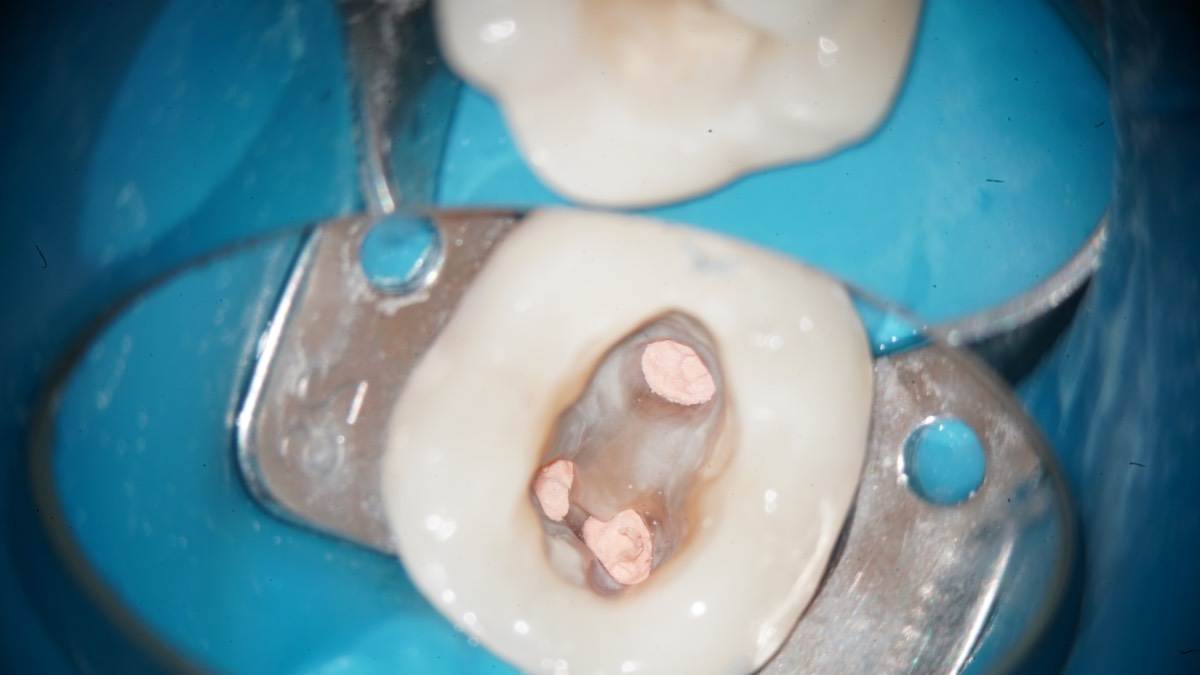

Гарриевич Опубликовано 31 января Автор Поделиться Опубликовано 31 января Когда в твоем кресле оказывается пациент с редким заболеванием «стоматолог-терапевт» работать всегда… легче. Именно! Потому что ты на 100% уверен, что этот человек понимает разницу между «гарантия» и «прогноз», а он на 100% уверен, что ты тот кто ему нужен. Зуб 4.7 со сложной анатомией, ступенькой в мезиальной системе, двойным изгибом, пропущенным каналом и апикальным периодонтитом. Реколл 1 год И сам осмотр через 1 год 4 1 1 Ссылка на комментарий

Гарриевич Опубликовано 2 февраля Автор Поделиться Опубликовано 2 февраля @Carioznik да, им проще сглаживать ступень, проходить длинные каналы, в дистальном отделе удобнее фиксировать файл 1 1 Ссылка на комментарий